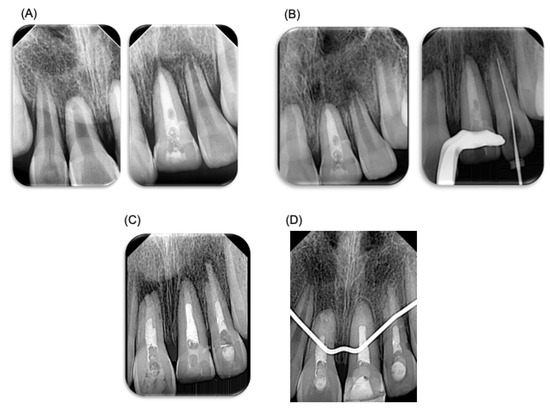

Figure 1.

Odontology treatment of patient. Management of dentoalveolar trauma in pediatric patient. (A) Photograph of dentoalveolar trauma in pediatric patient. (B) Reimplantation of tooth 22. (C) Management of trauma using a wire–resin splinting technique. (D) Periapical X-ray after splinting treatment.

For the treatment plan, digital periapical radiographs (radiovisograph, Woodpecker Medical Instrument Co., i-sensor H2, Guilin, Guangxi, China) were taken of the trauma area. The area was carefully rinsed with saline solution (PiSA, Guadalajara, Jalisco, Mexico), and anesthesia (articaine 4%, ZEYCO, Zapopan, Jalisco, Mexico) was administered using an infiltrative technique. Curettage of the socket was performed for the reimplantation of tooth 22, applying gentle digital pressure. A digital periapical radiograph was taken to confirm the placement. The same procedure was applied to the other avulsed tooth 11 (Figure 1). It is worth mentioning that the avulsed teeth were rinsed with saline solution before reimplantation. Tooth 21, which had suffered extrusive luxation, was washed with saline solution. A passive splint was made using 0.014 braided wire, extending to teeth 65 and 55 (ten teeth in total, from molars to upper molars). The splinting procedure involved cleaning the area, applying etching acid (3M, St Paul, MN, USA), drying, applying adhesive (3M, MN, USA), and photocuring for 20 s. The splint was placed passively, and fluid composite resin (3M, MN, USA) was used. Periapical radiographs were taken, and the area was sutured with 4-0 silk (ETHICON, Raritan, NJ, USA) using simple stitches (Figure 1). Post-treatment, the patient was prescribed the following medications: amoxicillin/clavulanic acid (400/57 mg/5 mL, every 12 h, for 7 days), acetaminophen (500 mg, every 8 h, for 3 days), ibuprofen (400 mg, every 8 h, for 3 days), and chlorhexidine 0.12% (Lacer, Barcelona, Spain) for 7 days. The patient was told to consume a soft diet for at least 3 weeks. In addition, the case was reviewed by an oral and maxillofacial surgeon regarding the proposed treatment plan (Department of Oral and Maxillofacial Surgery, Faculty of Dentistry, Autonomous University of San Luis Potosi, SLP, Mexico).